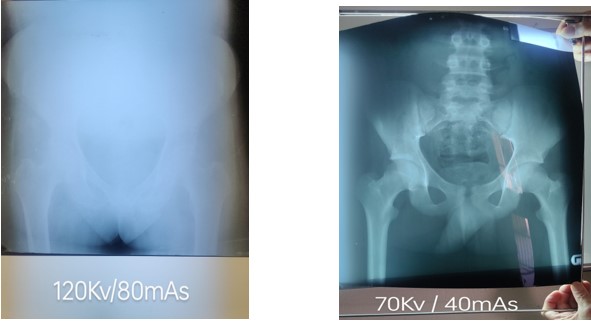

We noted fairly quickly that the exposure factors were very high. This was primarily due to having very old cassettes with a blue film/screen combination and out of date chemistry. We had taken a good selection of green cassettes and Stella kindly ordered the necessary green films.

This subsequently resulted in over 50% reduction in x-ray exposures.

Original quality Much improved image using less than half the dose!

The combination of new faster cassettes and the automatic processing of images has resulted in highly improved diagnostic images.